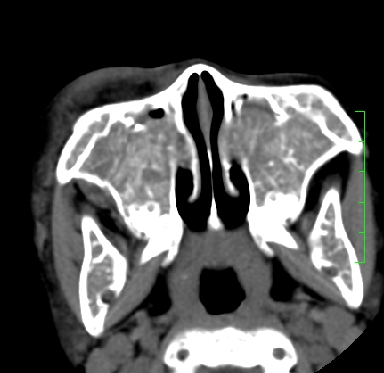

标题: PED1889:上颌窦病变

m,10y,外伤做ct

骨纤?

支持;骨纤,有皮肤色素沉着,性早熟时为albright综合征。

霉菌性鼻窦炎

骨化性纤维瘤可能性大。(与骨纤的鉴别:常见于面颅骨,多骨发病)